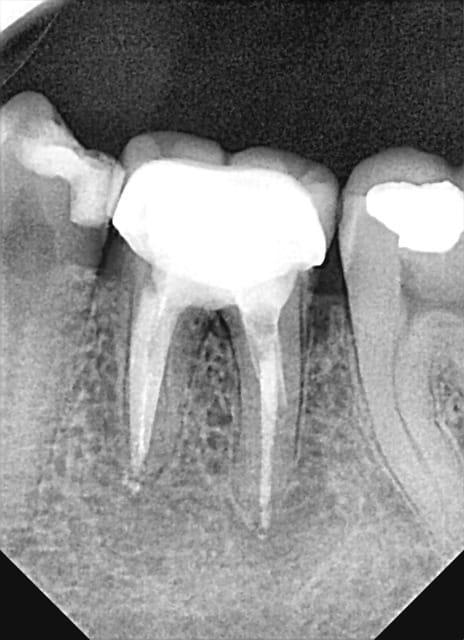

UN exemple de RTE

dépose inlay+couronne en 2009

retraitement sous digue indispensable(même sur dents antérieures la digue ce n'est pas pour faire jolie,c'est pour permettre à l'hypochlorite de rester à demeure tout le long du retraitement;il faut que çà "baigne" pour avoir une chance de

guérison apicale)

ici traitement sous hypo+digue +r-endo;il y a un dépassement léger au périapex

en 2015 guérison apparente du périapex(1h30 de retraitement!)

la dépose de l'inlay avec des ultrasons;désobturation acétate éythyle r-endo gutta compactage mac spadden

5eme photos en2009 et 2010;la dernière en 2015